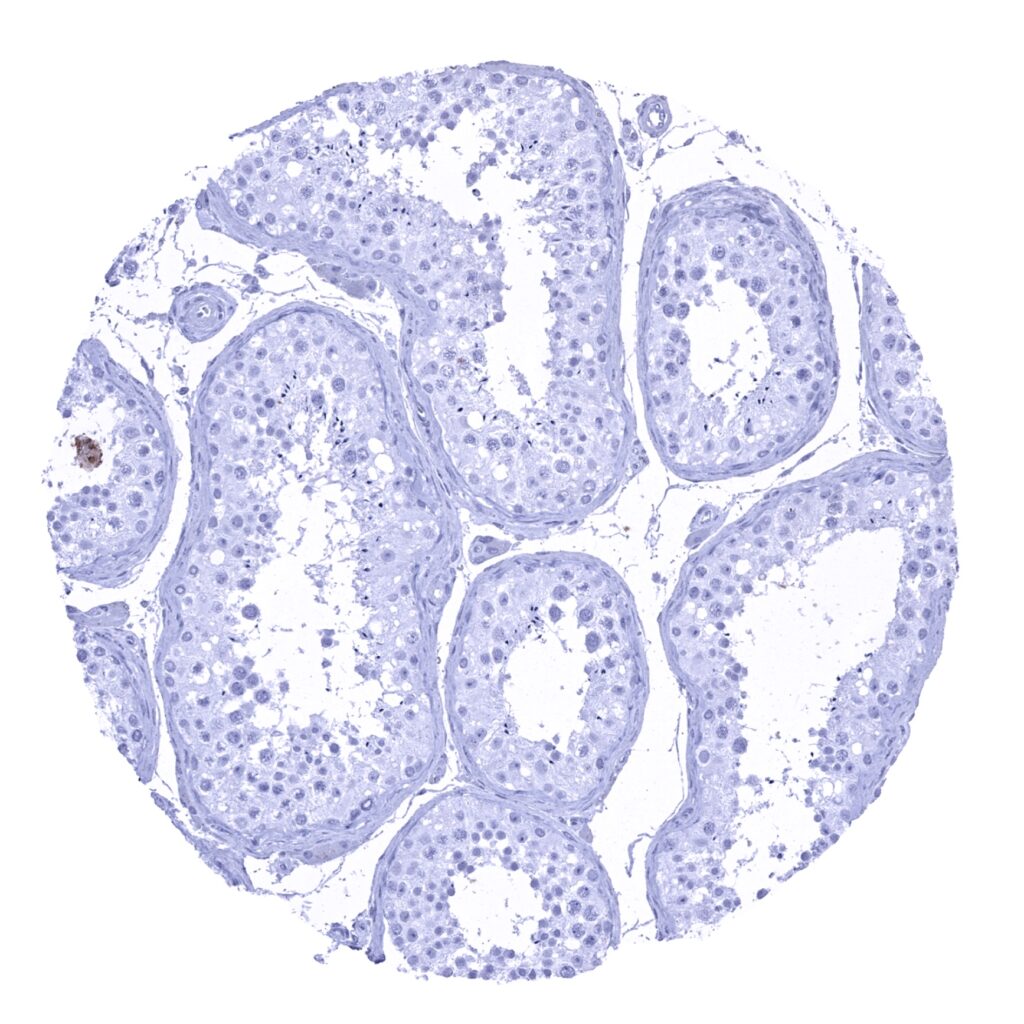

Epididymis